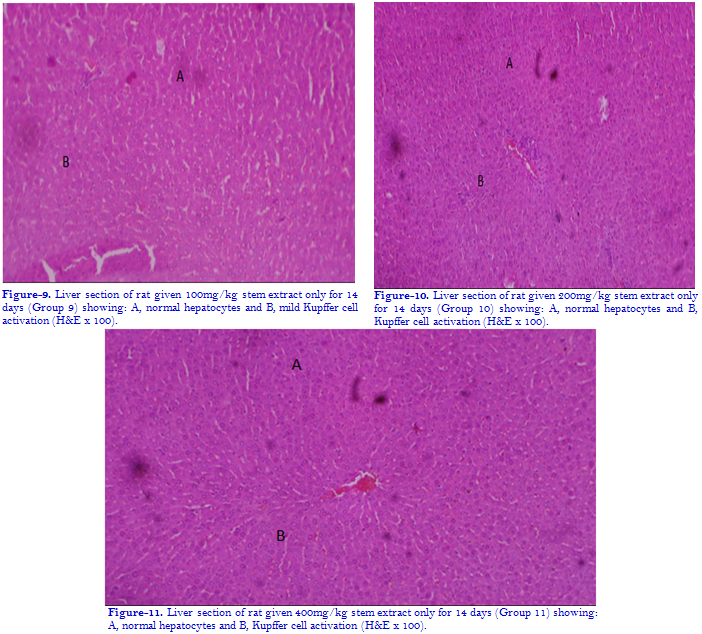

3.2. Effect of Ethanol Stem Bark Extract of Irvingia gabonensis O’Rorke Baill on Liver Histology of Experimental Rats in Presence or Absence of Sodium Arsenite Toxicity

Intoxication of the experimental animals with sodium arsenite (SA) for a period of 14 days  induced severe vascular ulceration, congestion perivascular infiltrates of inflammatory cells and Kupffer cell activation which are features of portal hepatitis in the liver. On administration of graded doses (100, 200, and 400mg/kgbw) of ethanol stem bark extract of Irvingia gabonensis O’Rorke Baill both simultaneously and after 14 days of SA exposure (post-treatment), there was mild amelioration of the hepatitis with the post-treatment and a better amelioration with the simultaneous administration. The results are shown in the photomicrographs.

Histopathological assessment of liver tissues showed that there were no visible lesions in the liver of the animals in the control group. In contrast, exposure to sodium arsenite alone produced vascular congestion and ulceration, infiltration of inflammatory cells and moderate Kupffer cell activation. On administration of graded doses of ethanol stem bark extract, 14 days later and simultaneously, there was mild amelioration of the hepatitis with the first modality and a better amelioration with the simultaneous treatment. This is consistent with findings from previous studies on the hepatotoxicity of sodium arsenite [74, 75].